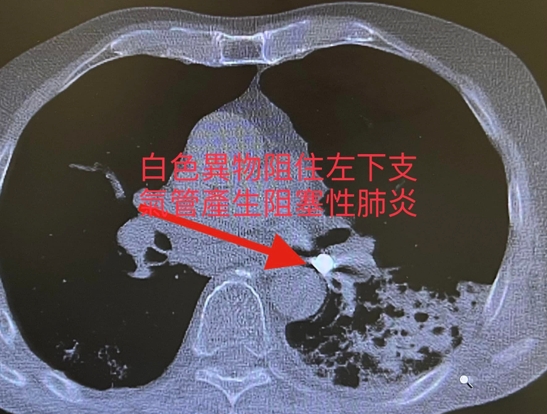

老人應該預防跌倒與嗆到才能延長壽命。 年紀大吞嚥困難常嗆到而不敢吃,產生營養不良。老是嗆入而產生吸入性肺炎而老是要住院治療,以前為了延長壽命減少嗆而接受插鼻胃管進食。但是現在為人性尊嚴與享受美食反對插鼻胃管,所以吸入性肺炎或意外嗆到而死案例增加。年紀大吃東西要小心 常常噎到甚至嗆進呼吸道。因為喉部肌肉萎縮與神經反射遲緩,食道蠕動較差所以導致吞嚥困難且易嗆進呼吸道(大的異物如假牙、骨頭等)而嚴重卡在在大氣管導致猝死。若中小異物卡在支氣管會產生塌陷與阻塞性肺炎,若睡覺口水嗆到至肺泡產生局部發炎,若是多次嗆至肺泡多次發炎產生肺纖維化。 吃東西假牙掉入左下肺支氣管產生阻塞性肺炎案例分享;九十五歲男性有抽煙史產生慢性阻塞性肺病病史且有攝護腺癌病史。最近因吃東西嗆到產生劇烈咳嗽與呼吸困難,且發現假牙不見了來院求診:胸部低劑量電腦斷層顧示右下肺有異物與阻塞牲肺炎(見圖)。緊急支氣管鏡檢並移出此異物。